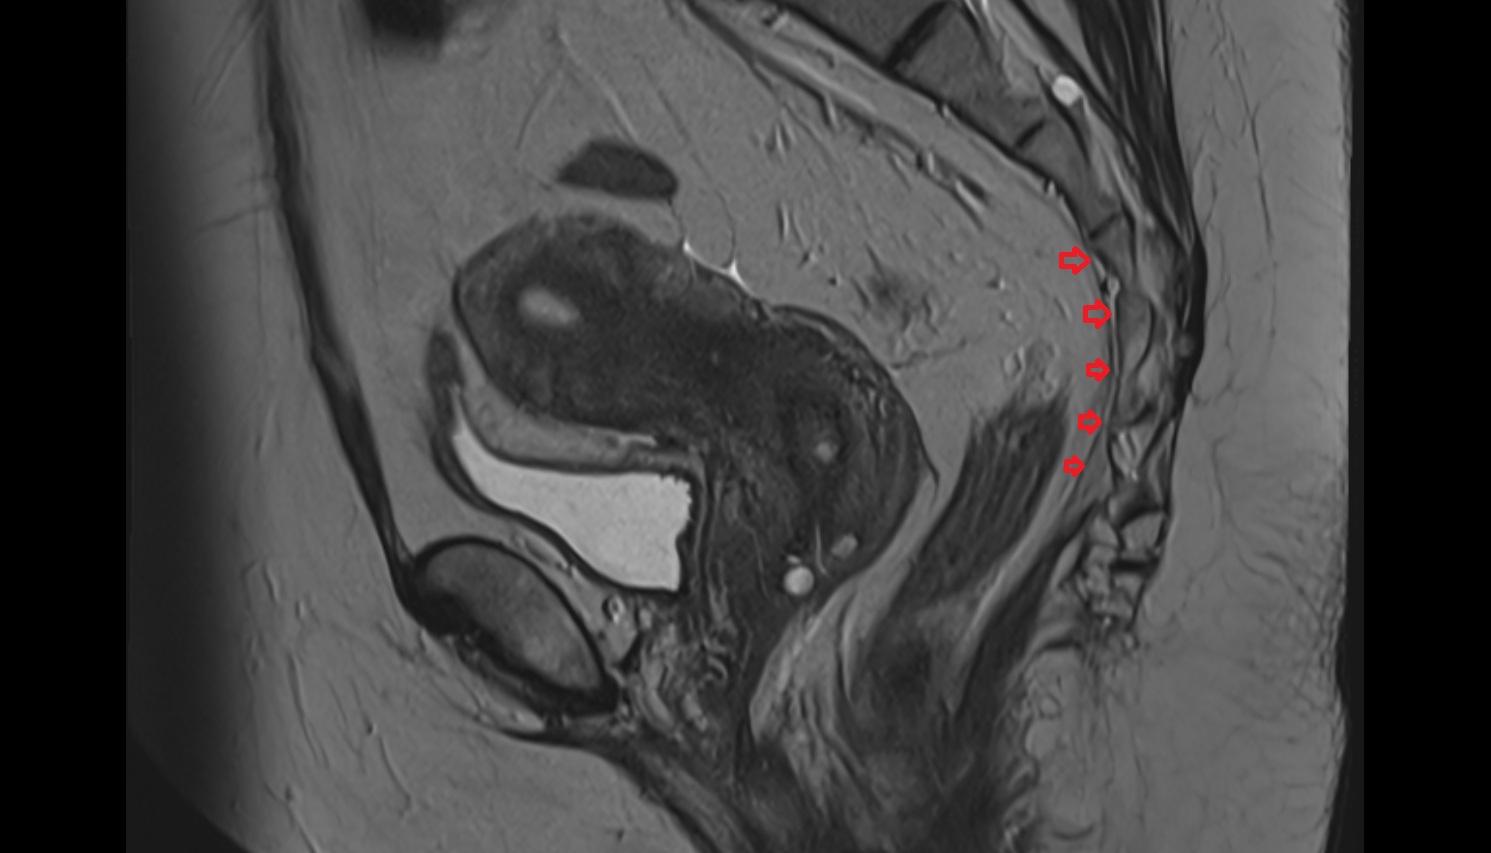

- Uterus

- Cervix of uterus

- Vagina

- Rectum

- Urinary bladder